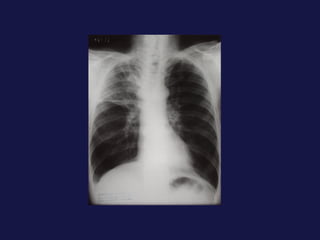

Carcinoma de células pequeñas   (18-25%). Peor pronóstico en  cuanto a supervivencia, responde bien a la quimioterapia. Variedad que mas da smes paraneoplasicos. 90% en bronquios centrales. SME de la vena cava superior. Localización central.

Carcinoma de célulaspequeñas (18-25%). Peor pronóstico en cuanto a supervivencia, responde bien a la quimioterapia. Variedad que mas da smes paraneoplasicos. 90% en bronquios centrales. SME de la vena cava superior. Localización central.

Tumor central. 60-75% próximos a los hilios. Epidermoides y células pequeñas. Agrandamiento asimétrico del hilio o masa de bordes espiculados. Atelectasia lobular, segmentaria o de todo el pulmón. Sobreinfección del parénquima distal y neumonía postobstructiva, a menudo abscesificada.

Tumor central. 60-75%próximos a los hilios. Epidermoides y células pequeñas. Agrandamiento asimétrico del hilio o masa de bordes espiculados. Atelectasia lobular, segmentaria o de todo el pulmón. Sobreinfección del parénquima distal y neumonía postobstructiva, a menudo abscesificada.